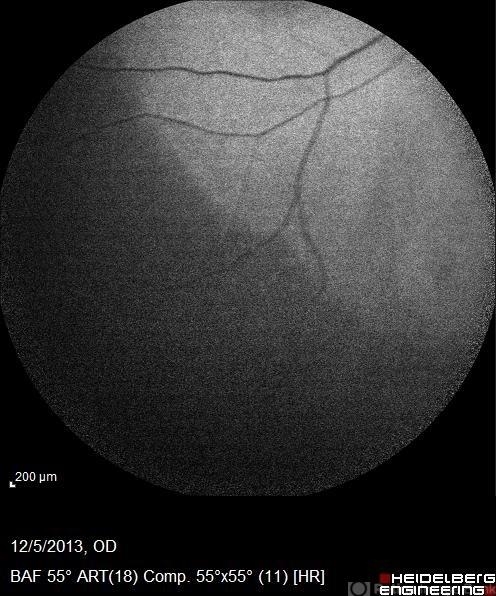

- acute zonal occult outer retinopathy (AZOOR), autofluorescence imaging

- Autofluorescence 12-5-13 AZOOR